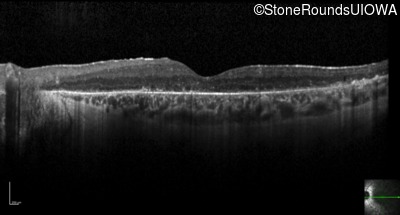

Optical Coherence Tomography - Right - 20/25 -1

Exemplar / OCT Stack

OCT Stack

Optical Coherence Tomography - Left - 20/50 -1